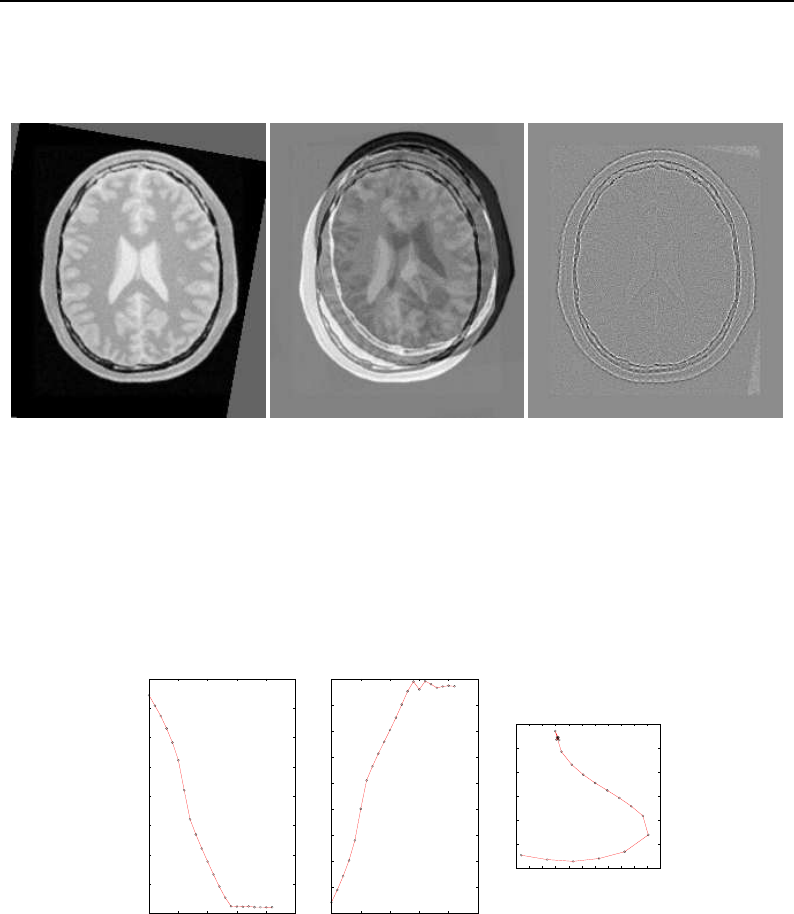

- Deformable Registration

- Demons Deformable Registration

- Visualizing Deformation fields